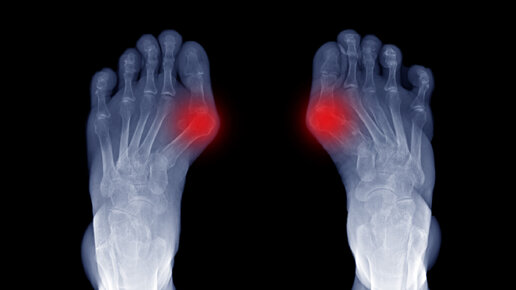

Болезненная деформация стопы — выпирающая косточка на большом пальце ноги — проблема, которая знакома многим женщинам. Почему появляется эта «шишка», можно ли затормозить ее развитие, как удалить «уродливый» нарост, который мешает носить элегантную обувь и портит походку? Современная медицина знает ответы на эти вопросы. Косточка на ноге — проблема не только косметическая. Деформация стопы не просто уродует ногу, но и ухудшает самочувствие из-за постоянной боли и воспаления. Выбор удобной, но при этом элегантной обуви превращается и вовсе в непосильную задачу...